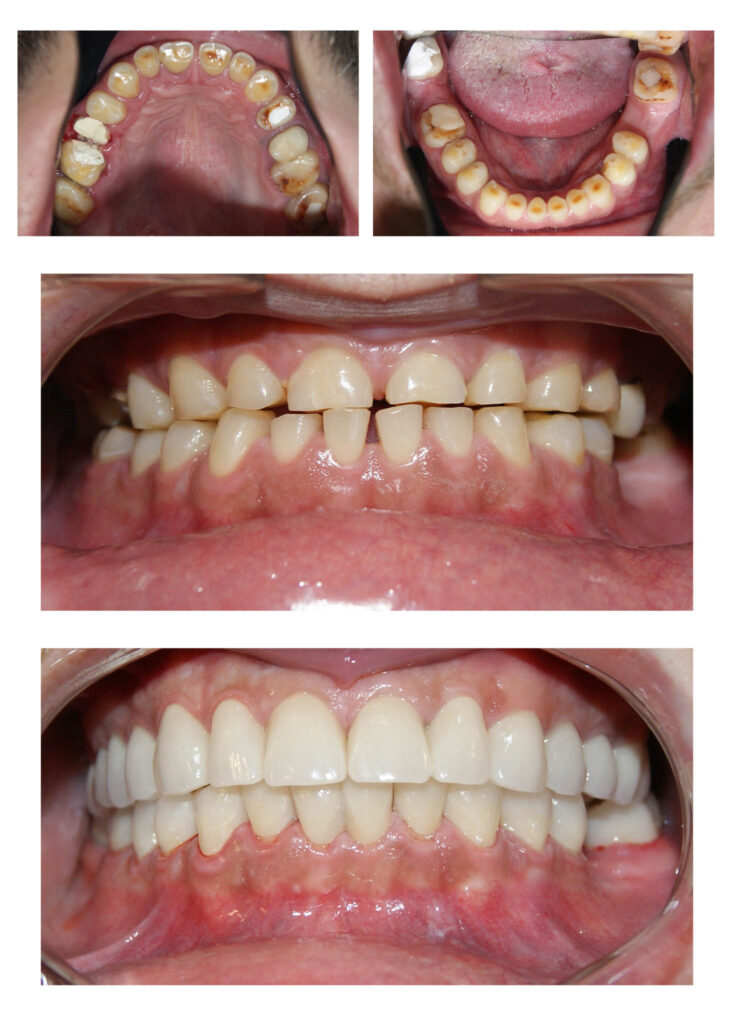

Un caz de o dificultate estestică majoră pe care l-am rezolvat cu succes împreună cu tehnicienii noștri. Am reușit să salvăm toți dinții deși erau destul de mult afectați și ulterior să îi îmbracăm cu coroane solo. Cromatica coronițelor este atât de potrivită încât în final nu se diferențiază de dinții naturali printre care sunt intercalate

Zirconiu stratificat

Înlocuire coroană metalo-ceramică cu o coroană de Zirconiu stratificat

Lucrare protetică din Zirconiu stratificat- integrare estetică- praguri minim invazive pe dinți tineri, vitali – gingii sănătoase